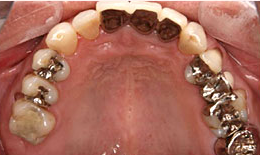

インプラント症例(20) 52歳 男性

治療前

下顎

保存困難な歯を抜歯後、インプラントを4本埋め込んで、セラミックスクラウンを被せた